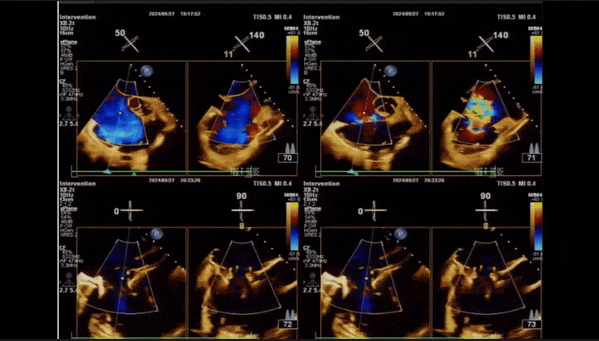

術后即刻返流

術后即刻經食道超聲可見,三尖瓣假體瓣膜位置合適,牛心包瓣葉運動狀態良好,開閉正常,瓣周及瓣葉對合緣處未見明顯返流,心電圖及心包狀態較術前無明顯變化。

術前術后返流情況對比